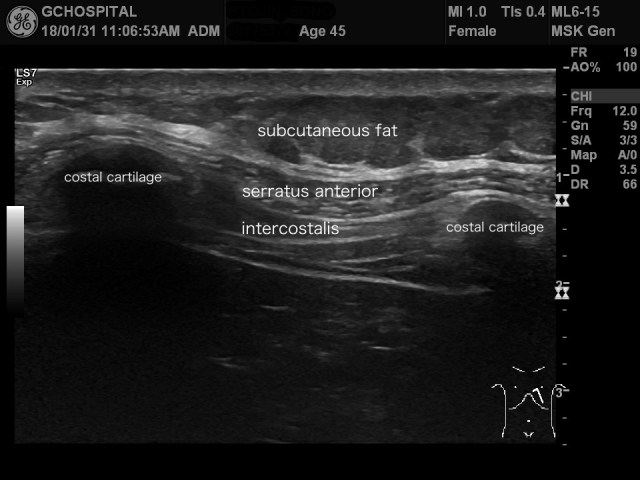

일단은 앞쪽 흉벽(anterior chest wall)에서 갈비뼈 사이의 구조물들을 초음파로 스캔하면 위와 같은 영상을 얻을 수 있습니다.

흉골에서 멀지 않은 늑골-연골 접합부(costochondral junction)에서 스캔한 영상이라 늑골 대신 내부에 일부 골화가 진행된 늑연골(costal cartilage)이 보이고, 늑골-연골 접합부 사이에는 늑간근이, 앞쪽으로는 serratus anterior muscle이 보입니다.

어지간히 뚱뚱하거나 초음파검사가 어려운 상황이 아니라면, 위의 영상에서처럼, 초음파로 늑간근의 세 층, 즉 external/internal/inner moste layer를 확인하는 것도 가능합니다. 위의 영상에서도 세 층을 구분하고 있는 fascia가 linear line으로 확인되고 있습니다.